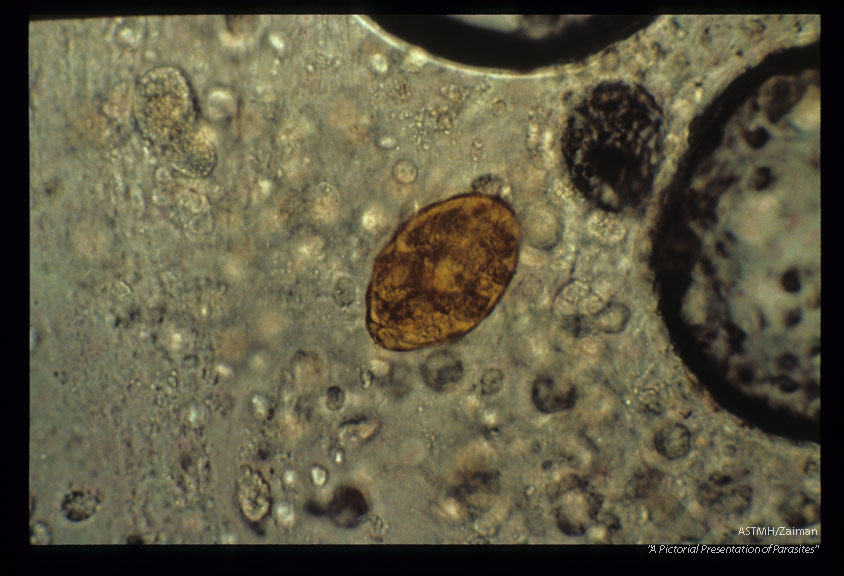

Egg in same sputum.

Paragonimus westermani

Description: Egg in same sputum.